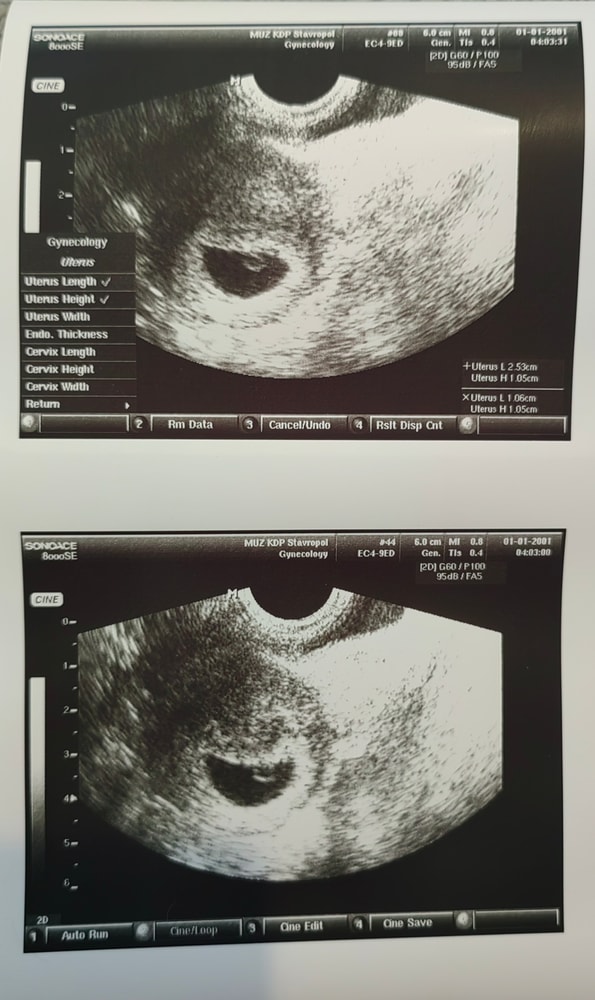

27 дпп УЗИ❤️

Результаты УЗИВсем привет) Я дождалась этот день😁 Как же было страшно и волнительно, зашла, легла, мне повернули экран, а там пустое плодное яйцо 😰 У меня сердце остановилось на мгновение😁 Но потом появился эмбриончик, и у него мерцало сердечко 🤞💞🙏❤️ И мне даже дали его послушать🥰 Я не верю, что это происходит со мной🙏 Врач УЗИ переживала вместе со мной😊 Какой же он там еще крошка❤️ интересно почему не измерили биение сердечка? (не знаю как правильно написать) и еще нашли кисту в правом яичнике

СБ+

ПЯ 18 мм

ЖМ 3.3

Эмбрион 4,9 мм